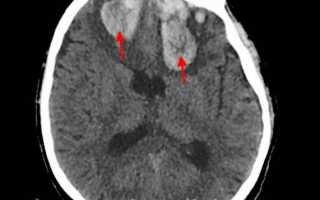

• КТ головного мозга. На томограммах внутримозговая гематома выглядит как очаг гомогенной плотности округлой или овальной формы. Если гематома возникла из-за ушиба головного мозга, она обычно имеет неровные контуры. Со временем плотность гематомы уменьшается до изоплотного состояния, соответствующего плотности мозговой ткани. Для малых гематом этот процесс занимает 2-3 недели, для средних — до 5 недель.